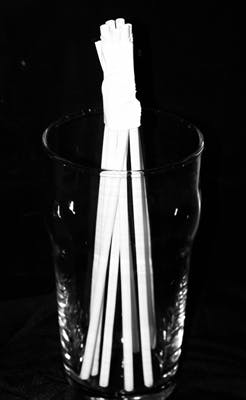

Figure 10: Straw simulation of inverse post distributions within tooth

Figure 8: Adhesive application